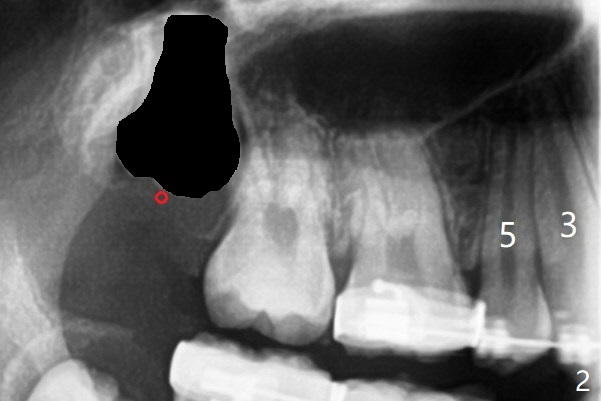

While the left posterior interdigitation is normal, the right is a half tooth off (Class II) 2.5 years post banding (16 years old, male, Fig.1). The upper midline remains left. The roots of the upper anterior teeth are within normal limit. UR8 will be extracted with bone graft (sticky bone; Fig.2). A 8 mm mini implant or a DIO 1-piece implant with ball abutment will be placed in the same appointment if possible (red circle). With a closed coil spring, UR3-7 or 1-7 will be distalized en bloc (Fig.3). Take photos for the occlusion: right, middle and left.